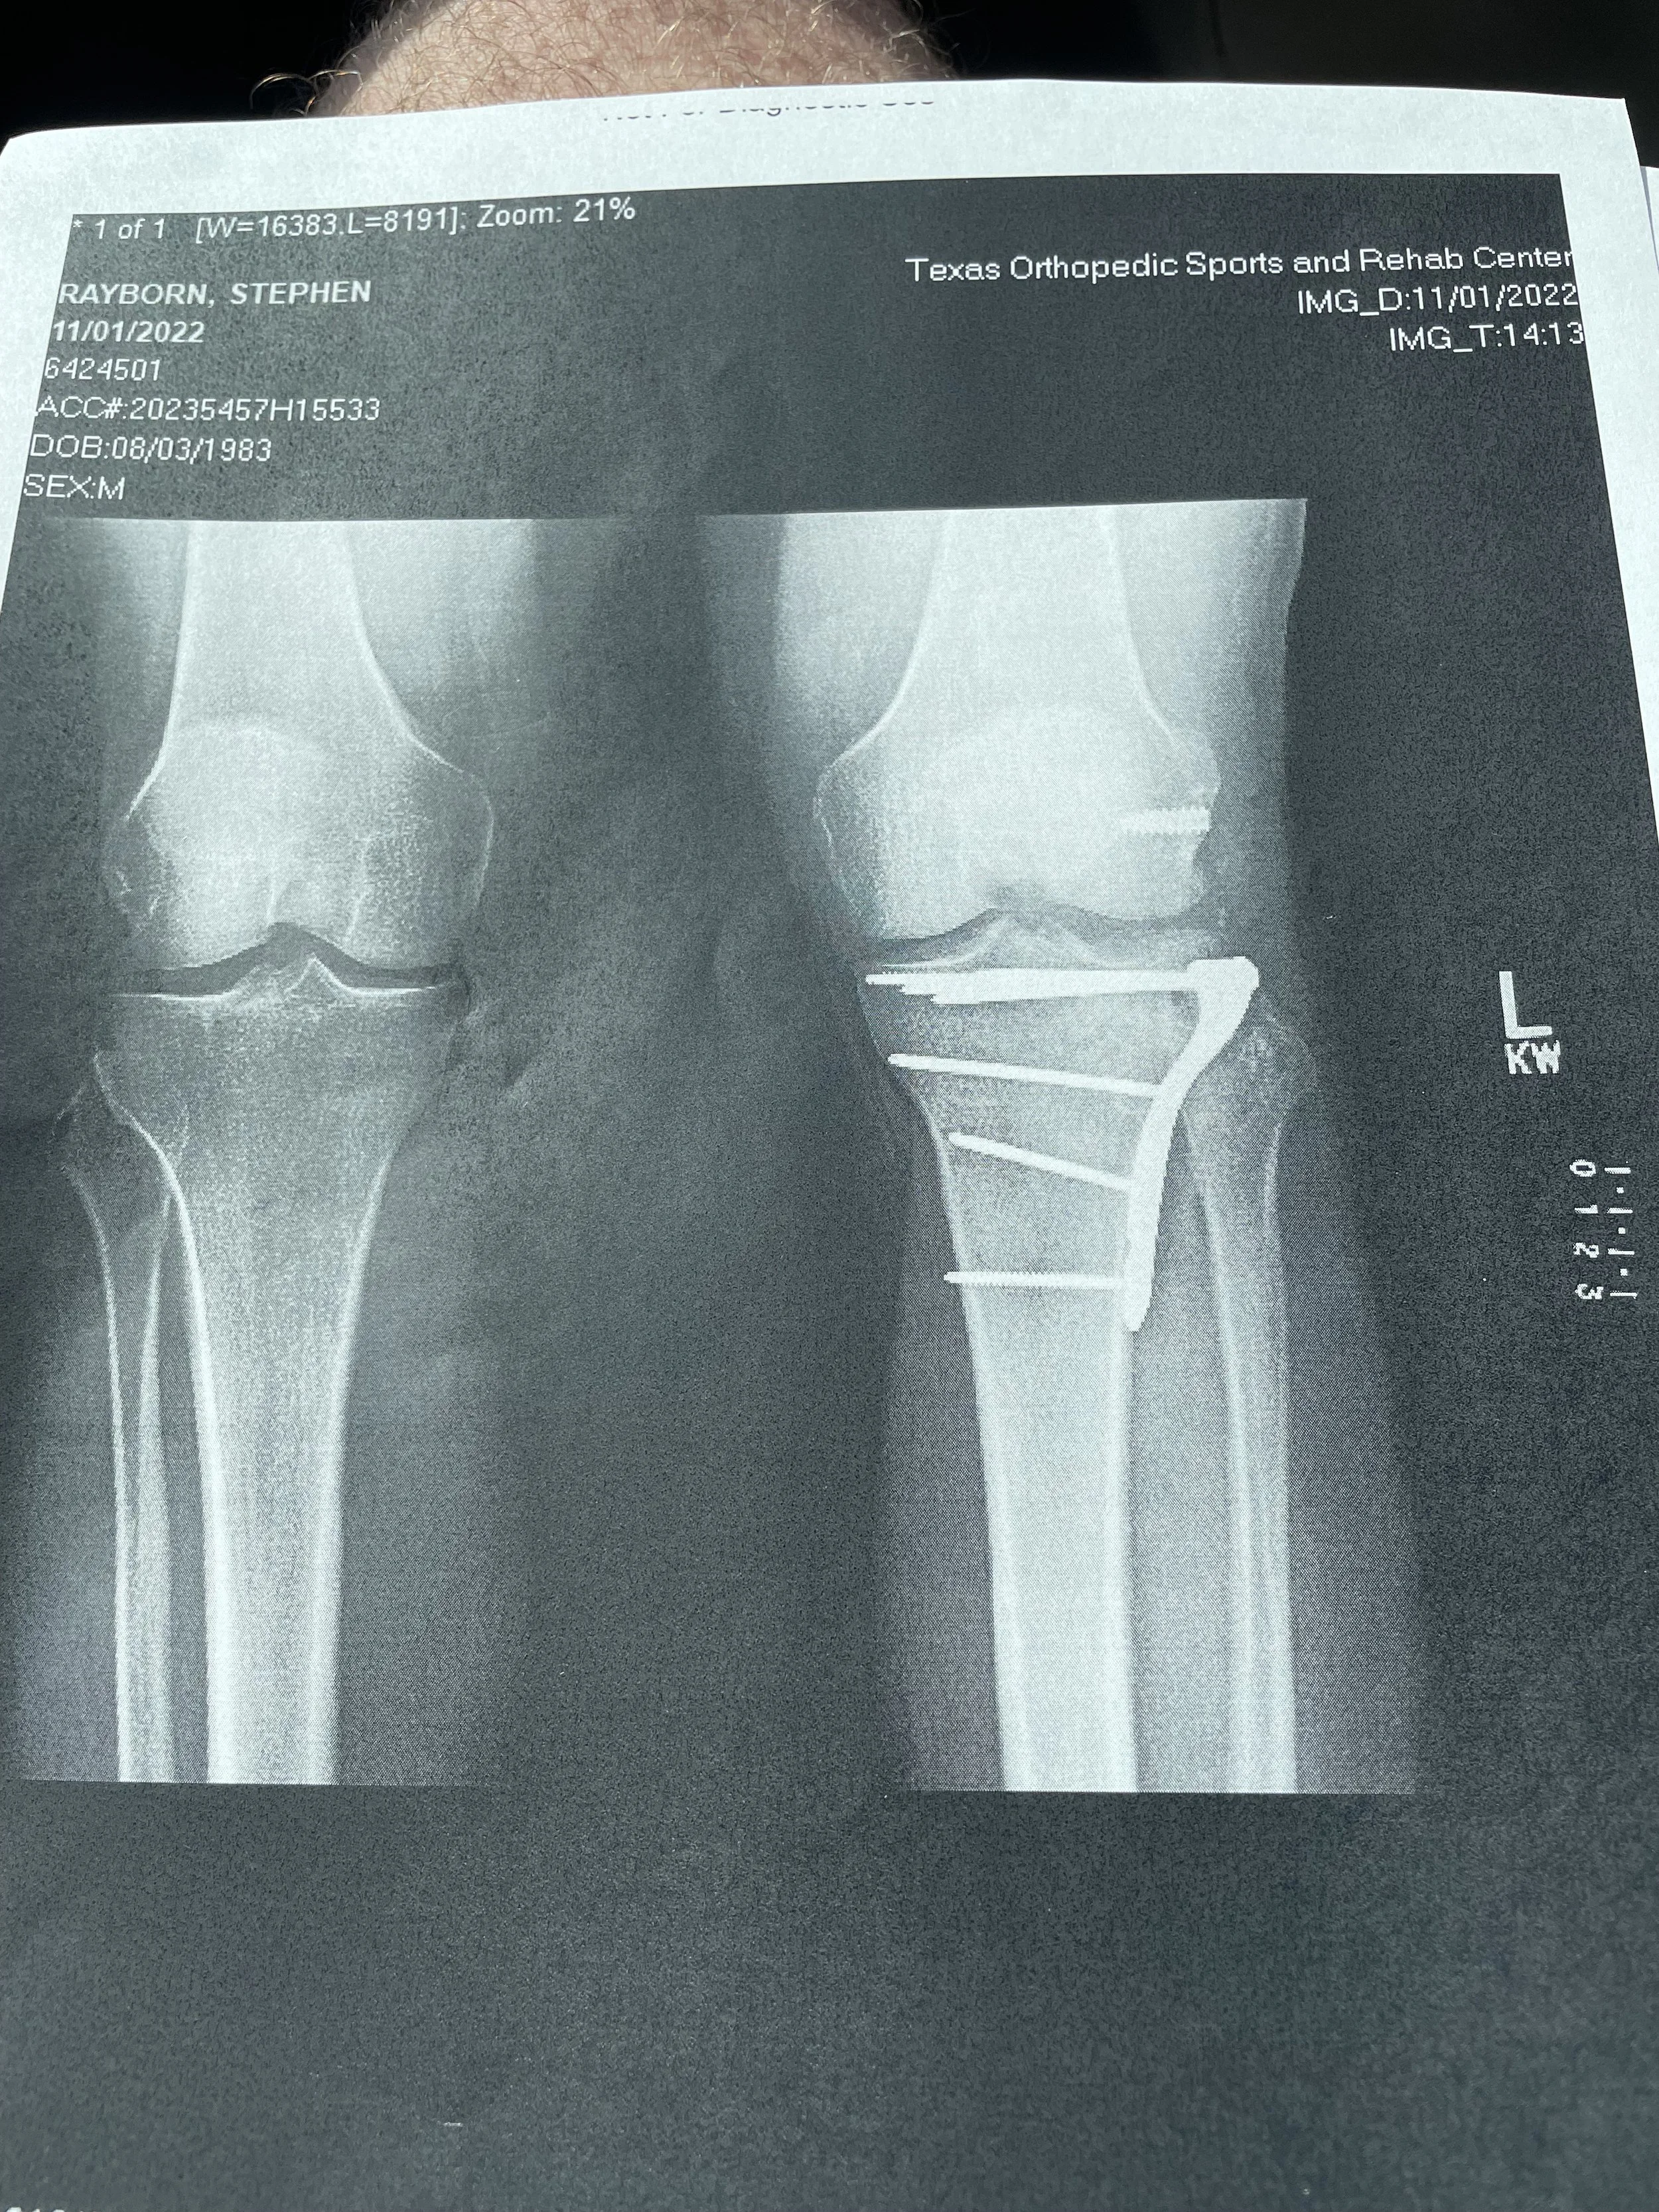

Founder, Stephen A. Rayborn, Esq’s left knee after surgery necissitated by a motorcycle accident.

Motorcycle accident claims are often complex, high-stakes, and heavily contested. They require careful preparation, strong evidence, and a clear strategy.

At Cypress Law, PLLC, these cases are approached with both professional experience and personal understanding. Having been through a motorcycle accident firsthand, the firms founder recognizes the realities riders face—from injury and recovery to dealing with insurance companies.